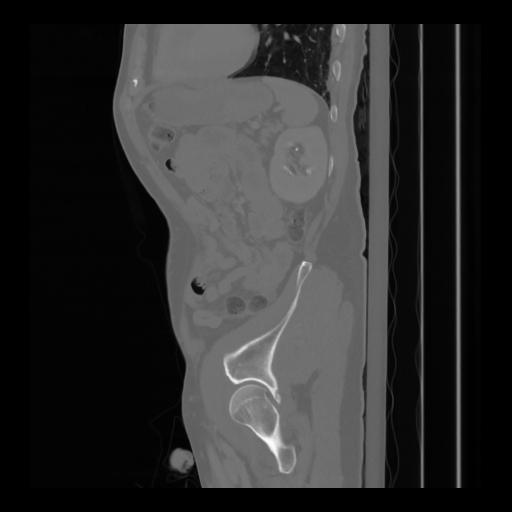

36 CUERPO,CE,Sagittal,3.000,CUERPO,Sagittal,